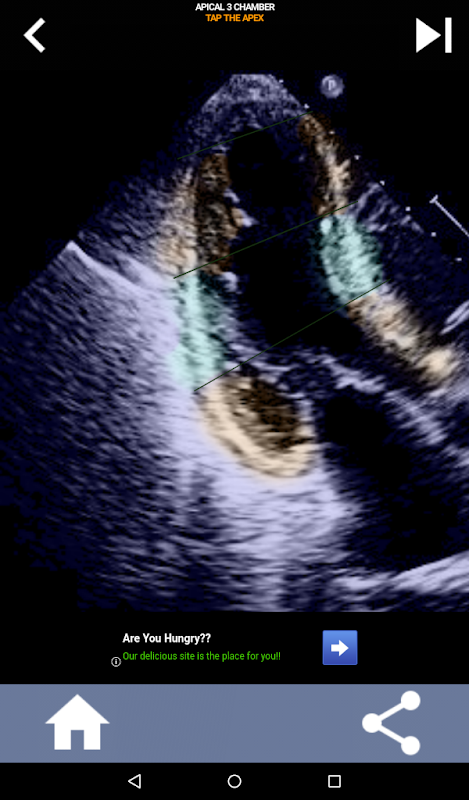

Визуальный подход к изучению сегментов сердца AHA на основе викторины: эхокардиография

Понимание сегментов сердца AHA (Американской кардиологической ассоциации) имеет первостепенное значение для кардиологического УЗИ, чтобы эффективно общаться с кардиологом, который пишет отчет. Зная конкретные анатомические области и соответствующие им сегменты, сонографист может точно описать и сообщить о любых аномалиях или результатах, обеспечивая четкое и краткое общение между обоими специалистами.

Это понимание становится особенно важным, когда кардиолог стремится установить точное местоположение проблемы или когда дежурный врач выявляет проблему в определенной области, побуждая сонографа точно отображать соответствующий сегмент, например, среднюю нижнюю стенку. Таким образом, всестороннее понимание сегментов сердца AHA является важным набором навыков.

Это приложение проверит ваши знания, используя реальные эхо-изображения, которые я часто считаю лучшим методом обучения.